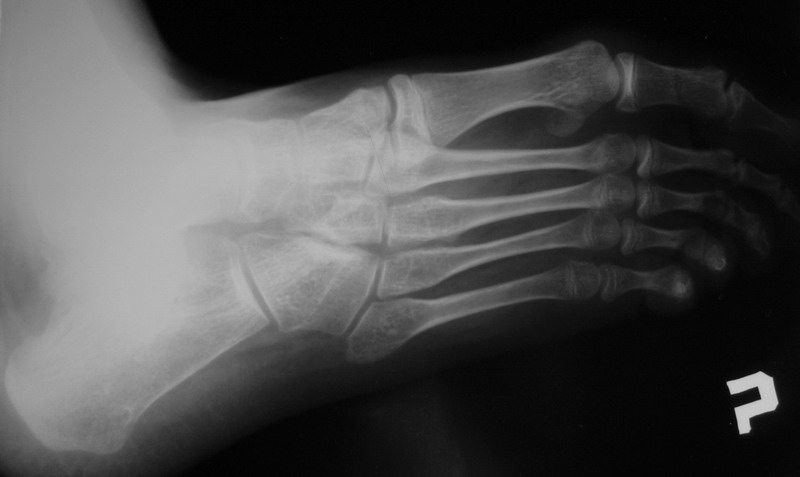

Пациент 15 л., болезнь Литтля, спастический нижний парапарез, интеллект высокий. Ребенок настроен на активный образ жизни. С недавнего времени начал ходить без дополнительной опоры. Появилась проблема с левой стопой - во время ходьбы опора приходится на смещенную кнутри таранную кость.

Может образоваться болезненный натоптыш или язва.Общепринятой операцией является трехсуставной артроде с мобилизацией таранной кости. Выполнять такую операцию у спастика и в раннем возрасте проблематично. Родстьвенники тем более готовы материально и морально осуществить хирургическое лечение за рубежом, если оно показано и возможно.Предпочтительно в Австрии и Германии. Если кто-то посоветует координаты таких клиник - были бы признательны.

Это типичная проблема со стопами у больных спастическим церебральным параличом. У Вашего пациента ситуация несколько запущена. Но решать её надо.

Стандартным хирургическим вмешательством в таком случае действительно является костнопластический корригирующий трёхсуставной артродез, вероятно с мягкотканным компонентом (эквинус). Такие операции без риска нарушения роста стопы можно выполнять с 12-летнего возраста. Так, что у Вашего пациента никакой опасности нет. Делать это можно где угодно по желанию родителей. Но, может быть не кидаться сразу за границу. У нас специалисты не хуже (а, может быть и лучше). Это и институт Турнера под С-Пб, и 18-я неврологическая больница в Москве (А.М.Журавлёв). Делаем такие операции и мы. Важный момент: после операции необходим полноценный специальный курс реабилитационного лечения, ортопедические пособия и наблюдение.

В приводимом случае, 15 летнему больному показан 3-суставной артродез. Однако считаю нецелесообразным существенно менять конфигурацию стопы, поскольку плоско-вальгусные деформации стоп это компенсаторный ответ на сгибательно-приводящие установки нижних конечностей. Изменение положения стоп(коррекция пронации) может нарушить сложившийся стереотип ходьбы, и ухудшить ситуацию.

1. in spastic flat foot deformity which is not fixed but passively stretchable in a normal position it´s possible to perform the calcaneal lengthening (Evans)

2. in fixed spastic flat foot in adolescent and adults you have to perform the correctice triple arthrodesis.

This is typical deformity for spastic diplegia in CP .In 15 years old boy the best option is tripple arthrodesis .